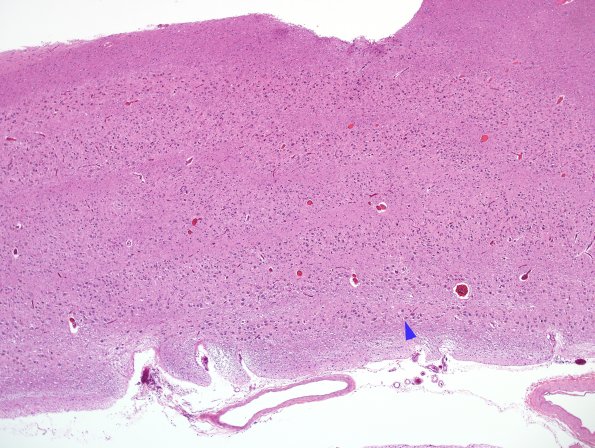

Washington University Experience | BASIC PROCESSES | Transneuronal Degeneration | 1B Lateral Geniculate Nucleus (LGN) H&E 4X

The normal LGN shows striking laminar distribution of neurons. The first layer of magnocellular neurons is marked (arrow) which is accompanied by one other layer of magnocellular neurons and four parvicellular layers. Enucleation results in lamina-selective degeneration.